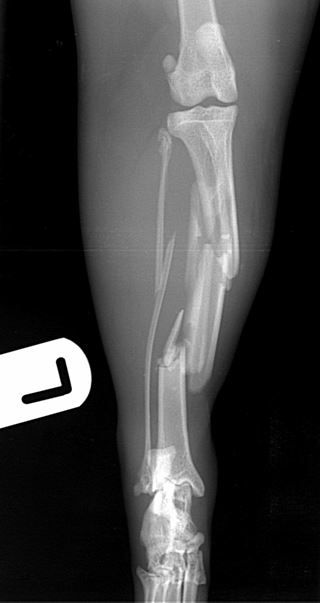

cat with comminuted fractures of the tibia, fibula and calcaneus         cat with comminuted fractures of the tibia, fibula and calcaneus

Fig. 1 A 6-year-old DSH cat with comminuted fractures of the tibia, fibula and calcaneus